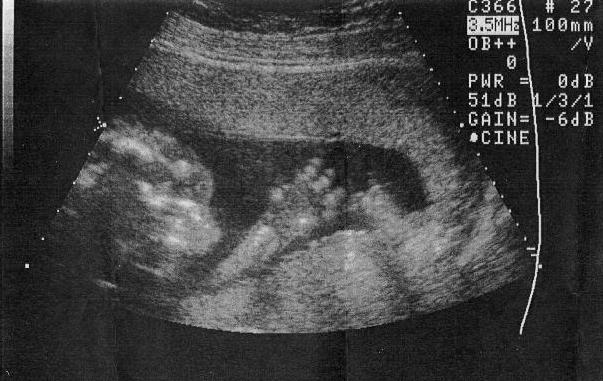

Galactosemia pictures: